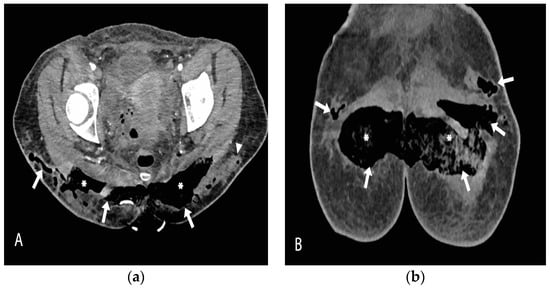

2. Case Report